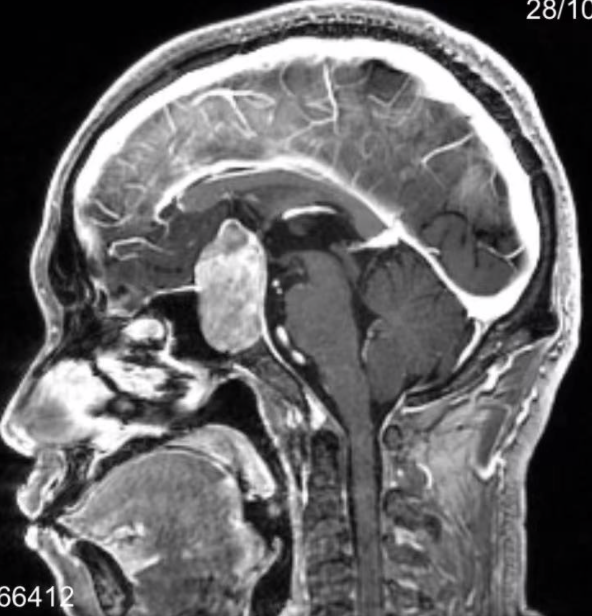

什么是泌乳素(PRL)型垂體腺瘤?

泌乳素型垂體瘤是指垂體分泌泌乳素(PRL)的腫瘤。一、女性泌乳素(PRL)型垂體瘤大部分為微腺瘤,見于20-30歲的青年女性。典型的癥狀為閉經(jīng)-乳溢-不孕三聯(lián)征。閉經(jīng)-不孕可由于高泌乳素血癥對(duì)性功能的抑制作用所致,表現(xiàn)于下丘腦水平,由于它干擾了正常的雌激素對(duì)促性腺激素釋放激素(LRH),分泌的正反饋?zhàn)饔枚翷H高峰與排卵。其中繼發(fā)性閉經(jīng)比較多見,約占90%。乳溢是本癥的主要表現(xiàn),多為觸摸性泌乳,約占50%-90%;性功能障礙約占60%,主訴多為性欲減退或缺如、性感喪失等。其他性腺功能減退的癥狀有經(jīng)期縮短、經(jīng)量稀少或過多、月經(jīng)延遲及不孕、乳腺萎縮,陰毛脫落,外陰萎縮、陰道分泌物減少等。女性青少年患者可發(fā)生青春期延遲、生長(zhǎng)發(fā)育遲緩及原發(fā)性閉經(jīng)。伴隨的代謝障礙表現(xiàn)如肥胖、水鈉潴留等癥候群。部分長(zhǎng)期高泌乳素血癥患者由于低雌激素血癥可發(fā)生骨密度減低,還可發(fā)生輕度多毛、痤瘡。二、男性泌乳素(PRL)型垂體瘤男性泌乳素瘤診斷時(shí)一般都較大了,常向鞍上發(fā)展,但相對(duì)少見。主要表現(xiàn)為性功能減退,約占83%.,可為完全性或部分性。比如程度不等的性欲減退、陽痿,男性不育癥及精子數(shù)目減少。由于癥狀進(jìn)展緩慢且有較大的波動(dòng),不易引起患者注意,所以很多患者發(fā)現(xiàn)的都較晚,發(fā)現(xiàn)時(shí)影像學(xué)檢查已多為大腺瘤,神經(jīng)壓迫癥狀較明顯。體格檢查可發(fā)現(xiàn)患者胡須稀疏、生長(zhǎng)緩慢、陰毛稀少、睪丸松軟。男性青少年患者青春期發(fā)育及生長(zhǎng)發(fā)育停止,體態(tài)異常和睪丸細(xì)?。淮送獯蟛糠帜行曰颊邥?huì)有肥胖的情況。所以男性患者當(dāng)有上述表現(xiàn)時(shí)必要情況下建議行垂體激素及相關(guān)影像學(xué)檢查,早發(fā)現(xiàn)早治療。?

???催乳素(PRL)腺瘤是最常見的功能性垂體腺瘤,約占成人垂體功能性腺瘤的40%-45%,以20-50歲的女性患者多見,成人患者男女比例約1:10。女性癥狀主要是閉經(jīng)、泌乳、不孕。男性患者雄激素水平下降可導(dǎo)致性欲減退、陽萎、不育及骨質(zhì)疏松等。因男性患者癥狀隱匿且特異性低,常被忽視導(dǎo)致就診時(shí)間晚。診斷???結(jié)合癥狀和鞍區(qū)影像學(xué)檢查對(duì)疑診垂體催乳素腺瘤的患者,如果血清催乳素>100-200μg/L,并排除其他特殊原因引起的高催乳素血癥,則支持催乳素腺瘤的診斷。如血清催乳素<100μg/L,須結(jié)合具體情況謹(jǐn)慎診斷。藥物治療????【中國(guó)垂體催乳素腺瘤診治共識(shí)(2014版)】推薦對(duì)垂體催乳素腺瘤的首選治療仍然是藥物,目前多巴胺受體激動(dòng)劑主要有溴隱亭和卡麥角林。藥物能使絕大多數(shù)病人PRL水平正常和腫瘤體積顯著縮小,而且藥物治療適用于各種大小的腫瘤。(l)溴隱亭:服用方法:溴隱亭(2.5mg/片)治療的初始劑量為0.625-1.25mg/d,建議晚上睡前跟點(diǎn)心口服。每周間隔增加1.25mg直至達(dá)到2片/d或3片/d。通過緩慢加量計(jì)劃和睡前跟點(diǎn)心同服的方法來減少不良反應(yīng)。7.5mg/d為有效治療劑量,如果腫瘤體積和PRL控制不理想,則可以逐步加量至15mg/d。繼續(xù)加量并不能進(jìn)一步改善治療效果。因此,不建議15mg以上的大劑量,而是建議改為卡麥角林治療。(2)卡麥角林:服用方法:0.5mg/片的初始治療劑量為,每周0.25-0.5mg,劑量每月增加0.25-0.5mg直到PRL正常,很少需要?jiǎng)┝砍^每周3mg。對(duì)比溴隱亭,卡麥角林服用更方便,患者的耐受性更好,對(duì)溴隱亭耐藥的患者可選用卡麥角林治療。(3)藥物不良反應(yīng):溴隱亭的不良反應(yīng)包括:頭痛、頭暈,惡心、嘔吐、消化性潰瘍等消化道癥狀,鼻腔充血,便秘,體位性低血壓,嚴(yán)重的患者甚至?xí)霈F(xiàn)休克表現(xiàn);乏力、焦慮、抑郁、酒精不能耐受;藥物誘發(fā)垂體瘤卒中??溄橇值牟涣挤磻?yīng)同溴隱亭,消化道不良反應(yīng)比溴隱亭輕,其他包括精神疾病,潛在的心臟瓣膜病。(4)停藥:藥物治療的最大困難是停藥難,也就是撤藥后的長(zhǎng)期治愈率低,大部分患者需長(zhǎng)期用藥。即便PRL水平下降到正常范圍,仍需服用足量的藥物用以進(jìn)一步縮小腫瘤體積。當(dāng)PRL水平保持正常至少兩年,腫瘤體積縮小超過50%,才考慮逐步減量,因?yàn)樵谶@一階段,低劑量能維持穩(wěn)定的PRL水平和腫瘤大小。然而,停止治療可導(dǎo)致腫瘤的增大和高催乳素血癥的復(fù)發(fā)。基于這一原兇,對(duì)大或者巨大腺瘤患者藥物減量或停用后必需進(jìn)行嚴(yán)密隨訪。外科治療????垂體催乳素腺瘤選擇手術(shù)治療需根據(jù)以下情況綜合判斷:腫瘤大小、血催乳素水平、全身情況、藥物治療反應(yīng),患者的意愿以及對(duì)生育的要求。????絕大多數(shù)手術(shù)可以采用經(jīng)鼻手術(shù)入路,隨著現(xiàn)在外科技術(shù)的進(jìn)步,尤其是神經(jīng)內(nèi)鏡微創(chuàng)技術(shù)的進(jìn)步,經(jīng)驗(yàn)豐富的手術(shù)團(tuán)隊(duì)可以使經(jīng)蝶竇入路手術(shù)更精確、更安全、損傷更小、并發(fā)癥更少。有文獻(xiàn)報(bào)道,微腺瘤停藥后一年長(zhǎng)期緩解率也只有36%-40%,也就是說,60%的病人撤藥1-2年后會(huì)復(fù)發(fā)。而手術(shù)的長(zhǎng)期緩解率,對(duì)于微腺瘤可以達(dá)到60-90%。因此,外科還是藥物作為首選治療變得具有一定的爭(zhēng)議,經(jīng)蝶竇入路手術(shù)也是垂體催乳素腺瘤患者除藥物治療之外的另一選擇。????手術(shù)療效與手術(shù)者的經(jīng)驗(yàn)、腫瘤的大小、侵襲程度及病程有關(guān)。有經(jīng)驗(yàn)術(shù)者的垂體瘤手術(shù)并發(fā)癥發(fā)生率逐年下降,微腺瘤的手術(shù)并發(fā)癥發(fā)生率總體不超過5%,推薦患者到有豐富垂體瘤手術(shù)經(jīng)驗(yàn)的醫(yī)院完成手術(shù),這樣可以減少手術(shù)并發(fā)癥,保留殘存垂體功能,提高手術(shù)療效。